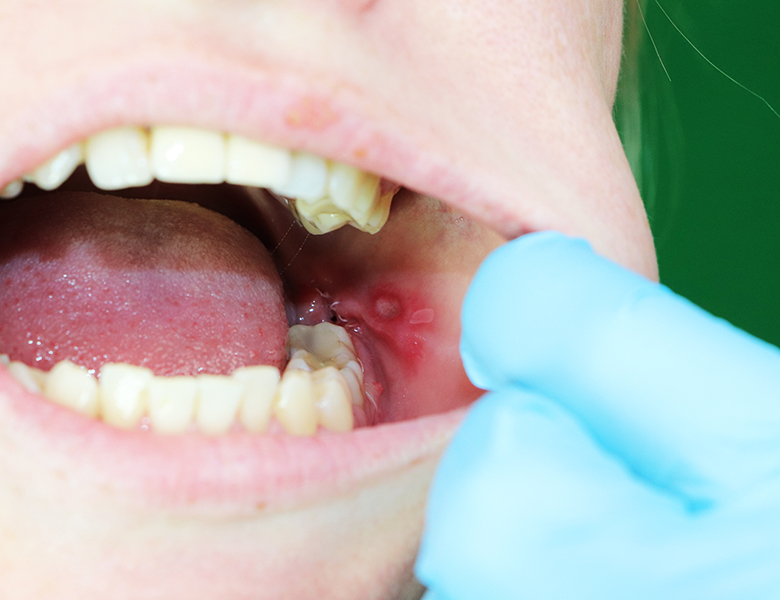

歯茎のポチッとした膨らみ(フィステル/根尖性歯周炎)

歯茎に白いニキビのようなデキモノができ、潰れると膿が出て、また膨らむ……という症状です。

過去に神経を抜いた歯の内部で細菌が繁殖したり、神経が自然に死んでしまったことで、膿が骨を突き破って出口(フィステル)を作っています。

痛みがないことも多いですが、実は「歯の根の先」に膿が溜まっているサインです。

当院の対応

マイクロスコープで根管内を精密に清掃する「精密根管治療」が必要です。

放置すると周囲の骨を溶かしてしまうため、早めの受診が大切です。